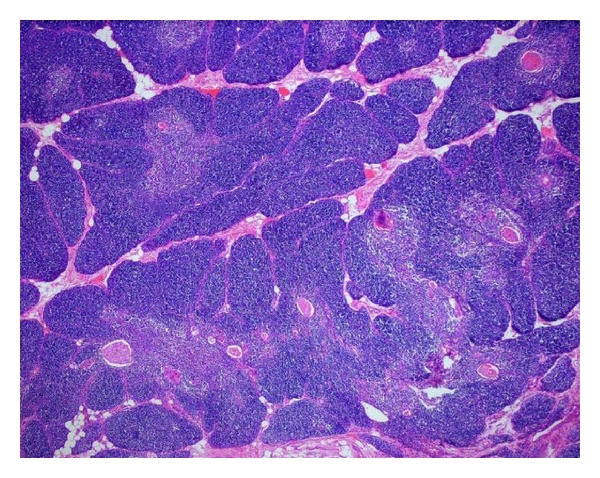

The resected specimens were sent to the Department of Pathology. Gross examination revealed a 11 : 9 : 1 cm-sized grey-coloured, firm, knotty mass weighing 53 g.

The mediastinal mass was essentially composed of histologically normal but increased thymic lobules with preserved corticomedullary differentiation, surrounded by mature fat with hyperaemic vessels enclosed. In the middle of the lobules, several enlarged Hassall corpuscles were observed. Adjacent to the thymic tissue three reactive lymph nodes were found.

Neither histologically nor immunohistochemically (staining with CD3, CD5, CD20, CD79a, p27, cyclin D1, and Ki-67) the suspicion for a posttransplant lymphoproliferative disease or malignancy could be affirmed (Figure 2).